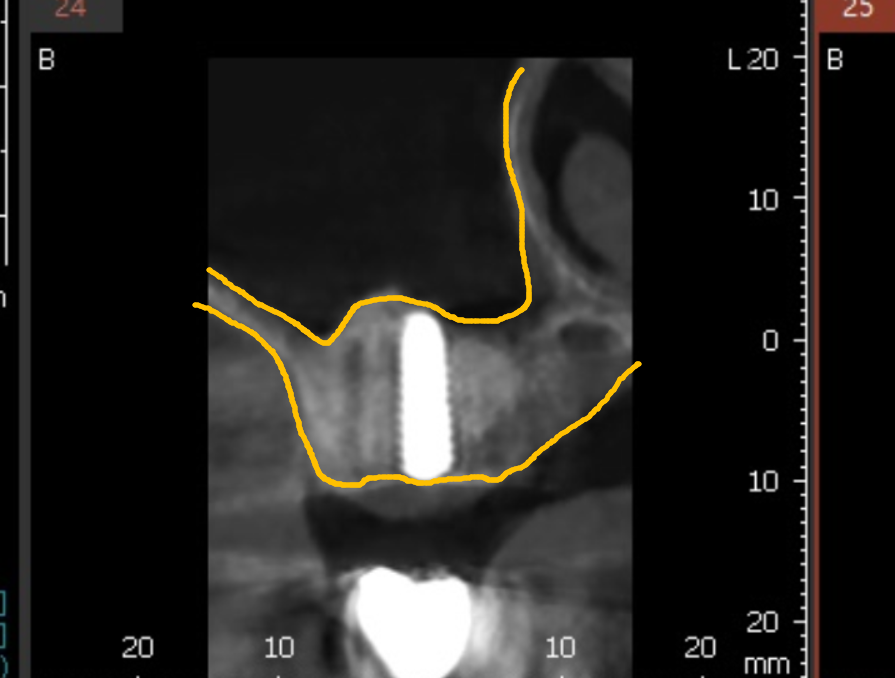

이렇게 상악동 안을 뼈로 채워 올릴 예정입니다.

식립 후 사진입니다.

식립 전에는 이 하얀 부분인 뼈가 굉장히 얇았는데,

식립 후에는 이 하얀 부분이 더 많아진 것을 볼 수 있어요.

이 하얀 부분이 바로 뼈이식을 한 부위입니다.